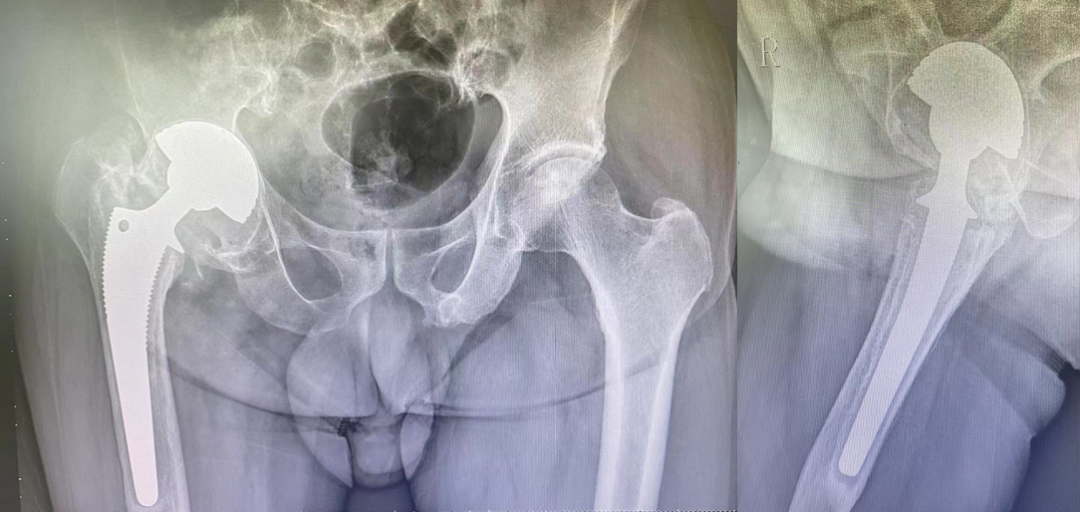

刘某,男,66岁,2007年因“股骨头缺血性坏死”行右侧人工全髋关节置换术,术后恢复良好。术后10年的某一天,突觉手术部位的轻微疼痛和不适,最初并未予以重视,但这种疼痛感周期性地出现,一拖再拖就拖了7年,直到旁人都看出来了步态异常,再三劝说,才找到我院柴生颋主任看诊,经过检查后,拍摄X线片提示髋臼杯透亮线形成,股骨柄远端髓腔硬化,假体下沉,考虑髋关节假体松动,建议患者住院治疗。

△患者手术前影像学资料